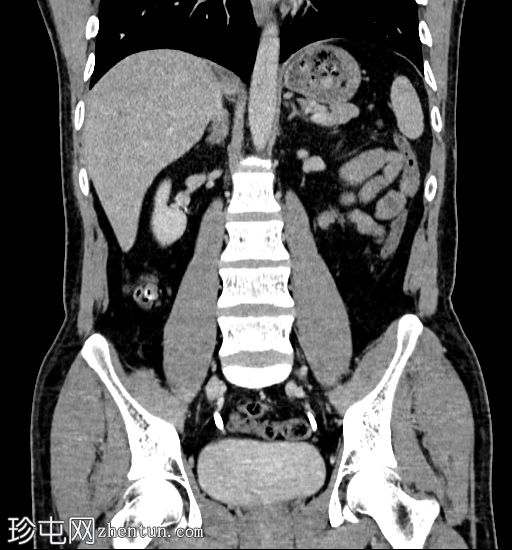

CT

轴位

平扫

双期增强

冠状位

左肾极间区钙化,形成一个相对下垂的平面,周围有非下垂的液体(乳状钙)。增强扫描显示该区域被造影剂充盈。

乳状钙是肾盏憩室的典型表现,本例亦是如此。